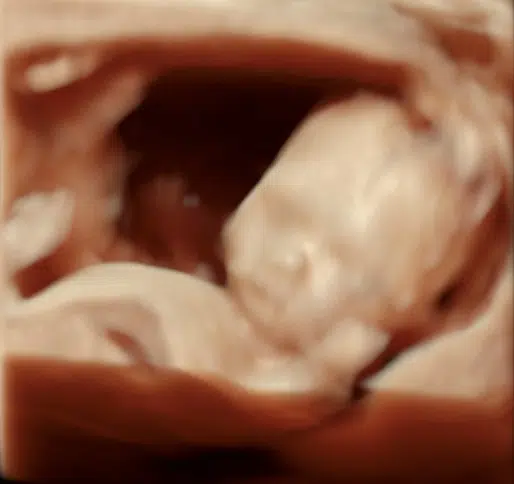

- I 3D ser du barnet, som det rigtigt ser ud inde i maven: Man kan se ansigtstræk, fingre, tæer og navlesnor. Sætter man 4D til, så filmer man og får bevægelser med.

En 3D-scanning giver dig mulighed for at komme endnu tættere på dit barn og opleve de små detaljer, der gør netop jeres barn unikt. Med naturlig 3D og HDlive får du billeder, som giver et livagtigt indtryk – næsten som at se dit barn i virkeligheden.

Når vi tilføjer den fjerde dimension (4D), bliver oplevelsen endnu mere levende, fordi du kan se dit barn bevæge sig. Ligger barnet godt, kan du måske opleve et smil, et gab, en lille hånd i munden eller andre personlige bevægelser.